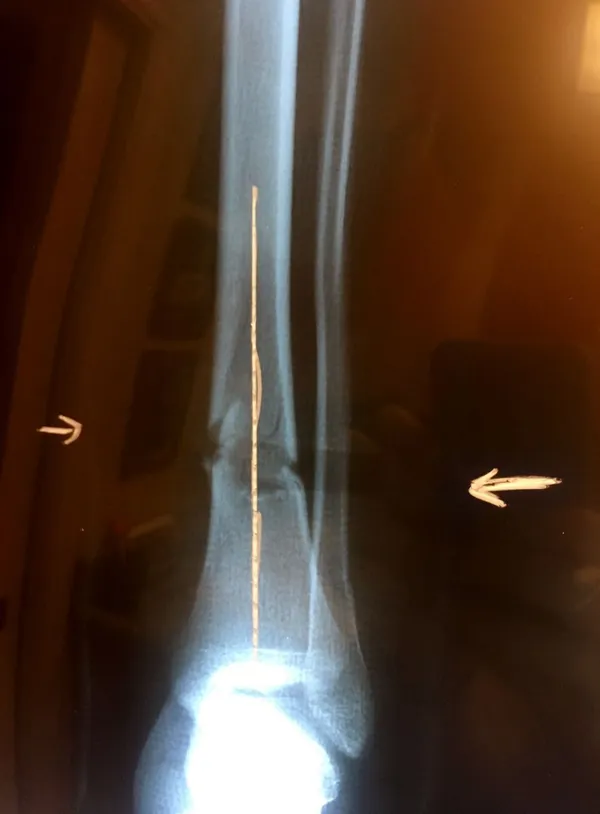

Below, Tibia and Fibula Fracture in a 16 year old injured skiing. The patient presented to the office 8 days after injury with a displaced fracture. The first 2 films show the displacement in the fracture of the tibia. After an above knee cast is appiled, the cast is wedged under fluoroscopy and new xrays show the near perfect reduction of the fracture. The white arrows show the area where the cast is wedged

Wedging of cast to keep a tibia fracture well aligned. We wedge the cast on a side if there is malalignment early on in the fracture healing to realign the fracture